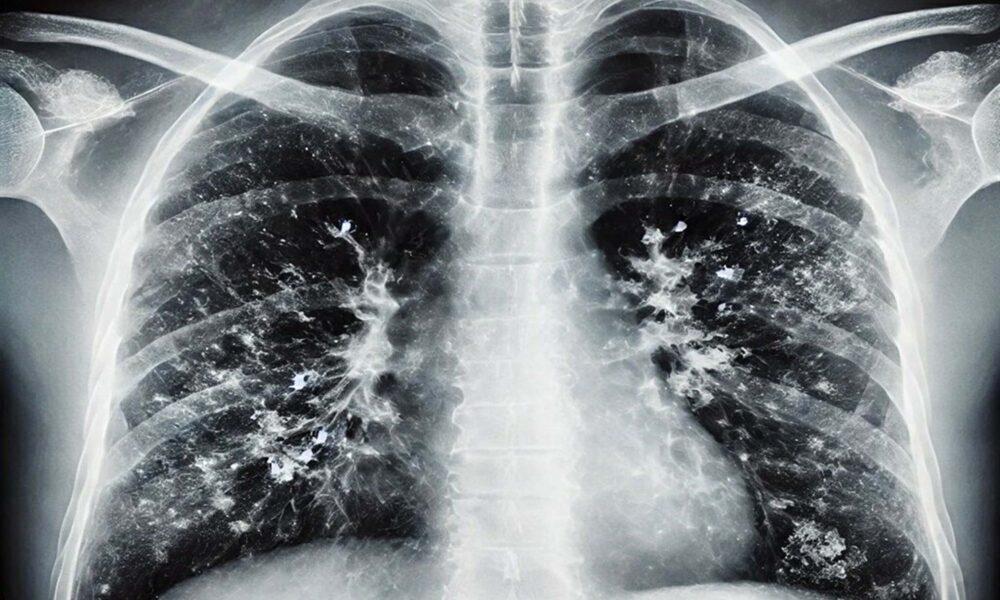

• Doktor Metin Kızılelma, kış aylarında solunum yolu enfeksiyonlarında artışın doğal ve bu enfeksiyonlardan korunmanın en önemli etkenin 'hijyen' olduğunu söyledi. Fotoğraf:Arşiv/İzmir,(DHA)